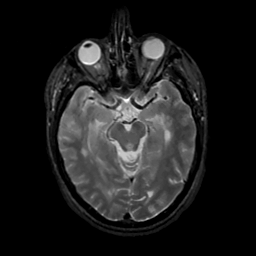

MR Study #13, May 19, 1991 -- Slice #20